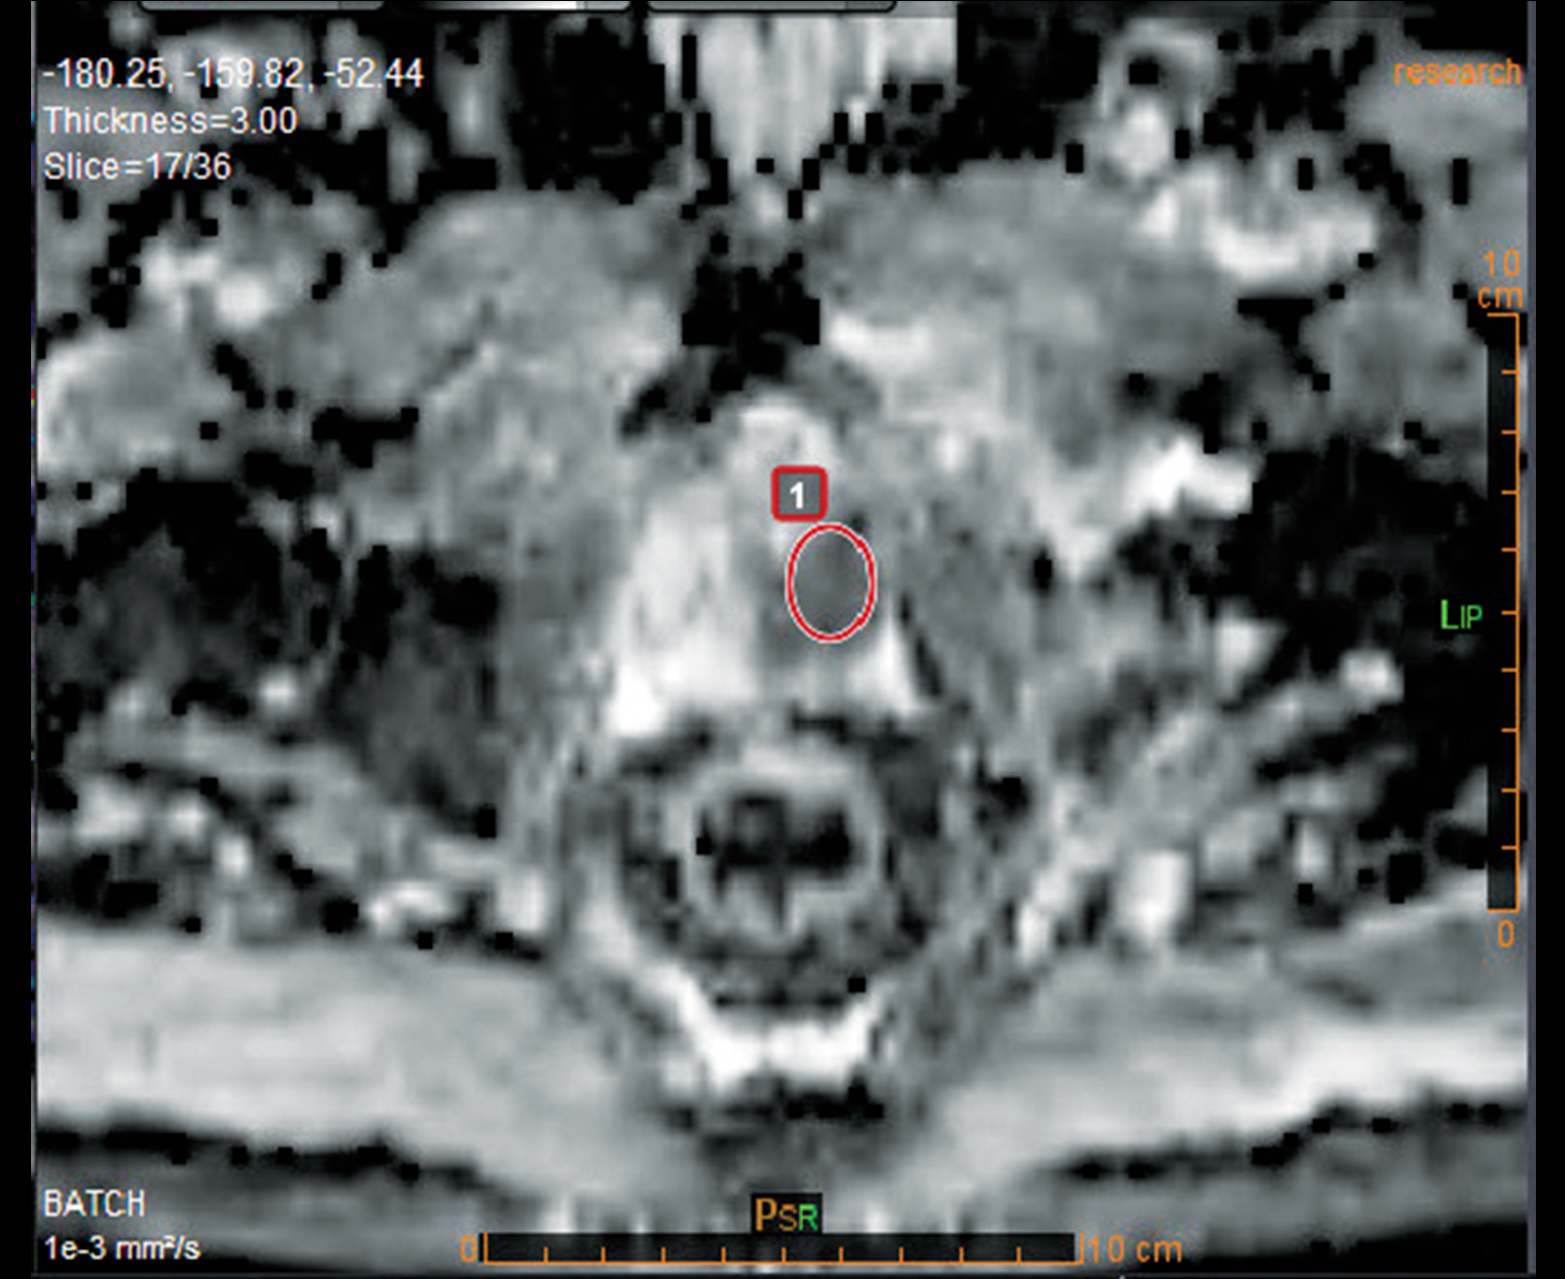

Расчет АЦП и других качественных и количественных карт

Многопараметрический просмотр и инструменты анализа для быстрой характеристики поражения